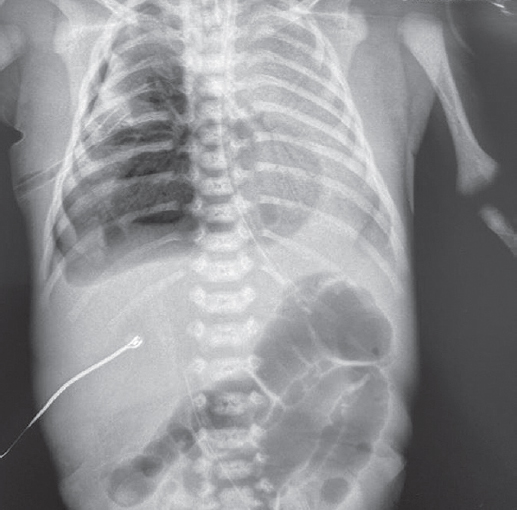

На третьи сутки жизни, через 12 ч после повторного введения порактанта альфа отмечается отрицательная динамика в виде снижения SpO2 до 78–84 %, прогрессирования цианоза кожи. Выполнена повторная рентгенограмма органов грудной клетки, наблюдается прогрессирование правостороннего пневмоторакса, снижение пневматизации левого легкого по сравнению со снимком сразу после введения порактанта альфа. Продолжено активное дренирование правой плевральной полости. В связи с артериальной гипотензией доза адреналина увеличена до 0,3 мкг/(кг · мин), на этом фоне гемодинамика стабильная, артериальное давление в пределах возрастной нормы. Учитывая снижение пневматизации левого легкого и прогрессирование дыхательной недостаточности, в левый главный бронх введен препарат берактанта. Во время манипуляции зарегистрировано снижение SpO2 до 45–50 %, нарастание цианоза кожи, в связи с чем манипуляция прекращена. Начато введение порактанта альфа в дозе 100 мг/кг в левый главный бронх. На фоне введения порактанта альфа наблюдается положительная динамика состояния пациента в виде увеличения SpO2 до 98 %. На рентгенограмме органов грудной клетки спустя 12 ч (рис. 5) после введения сурфактанта отмечается повышение прозрачности левого легкого.

Рис. 5. Рентгенограмма органов грудной клетки новорожденного после монобронхиального введения порактанта альфа

Fig. 5. Chest X-Ray of newborn after monobronchial administration of proractant alpha

На контрольной рентгенограмме на четвертые сутки жизни (рис. 6) сохраняется правосторонний пристеночный пневмоторакс, пневматизация левого легкого с улучшением. В связи с артериальной гипотензией продолжена постоянная инфузия допамина в дозе 15 мкг/(кг · мин), доза адреналина увеличена до 0,5 мкг/(кг · мин).

Рис. 6. Рентгенограмма органов грудной клетки новорожденного на шестые сутки жизни

Fig. 6. Chest X-ray of newborn on the sixth day of life

На девятые сутки жизни состояние ребенка стабильное, по газовому составу и КОС венозной крови компенсирован, параметры ИВЛ со снижением, плевральный дренаж удален (рис. 7).

Рис. 7. Рентгенограмма органов грудной клетки новорожденного на девятые сутки жизни

Fig. 7. Chest X-ray of newborn on the ninth day of life